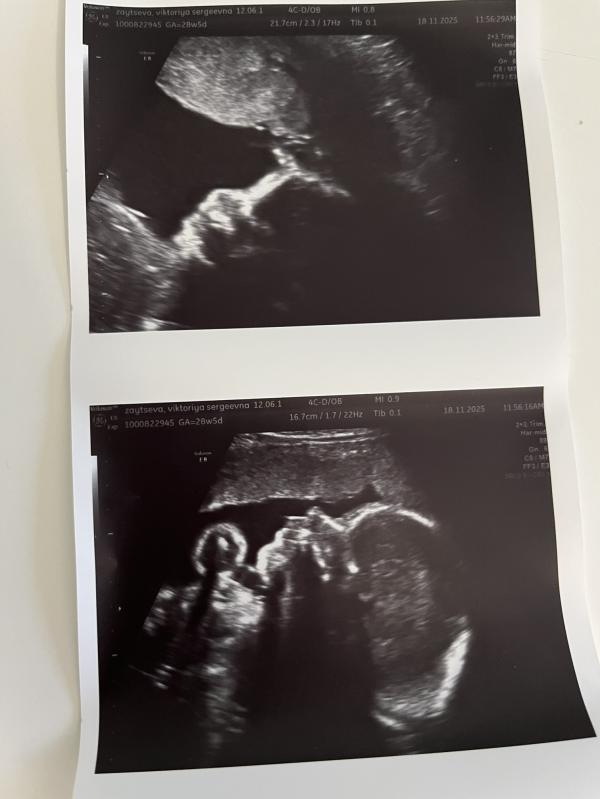

P.S наше первое фото 👇 сверху Есения , которая болеет еще , прячется 🫣, снизу Оливия.